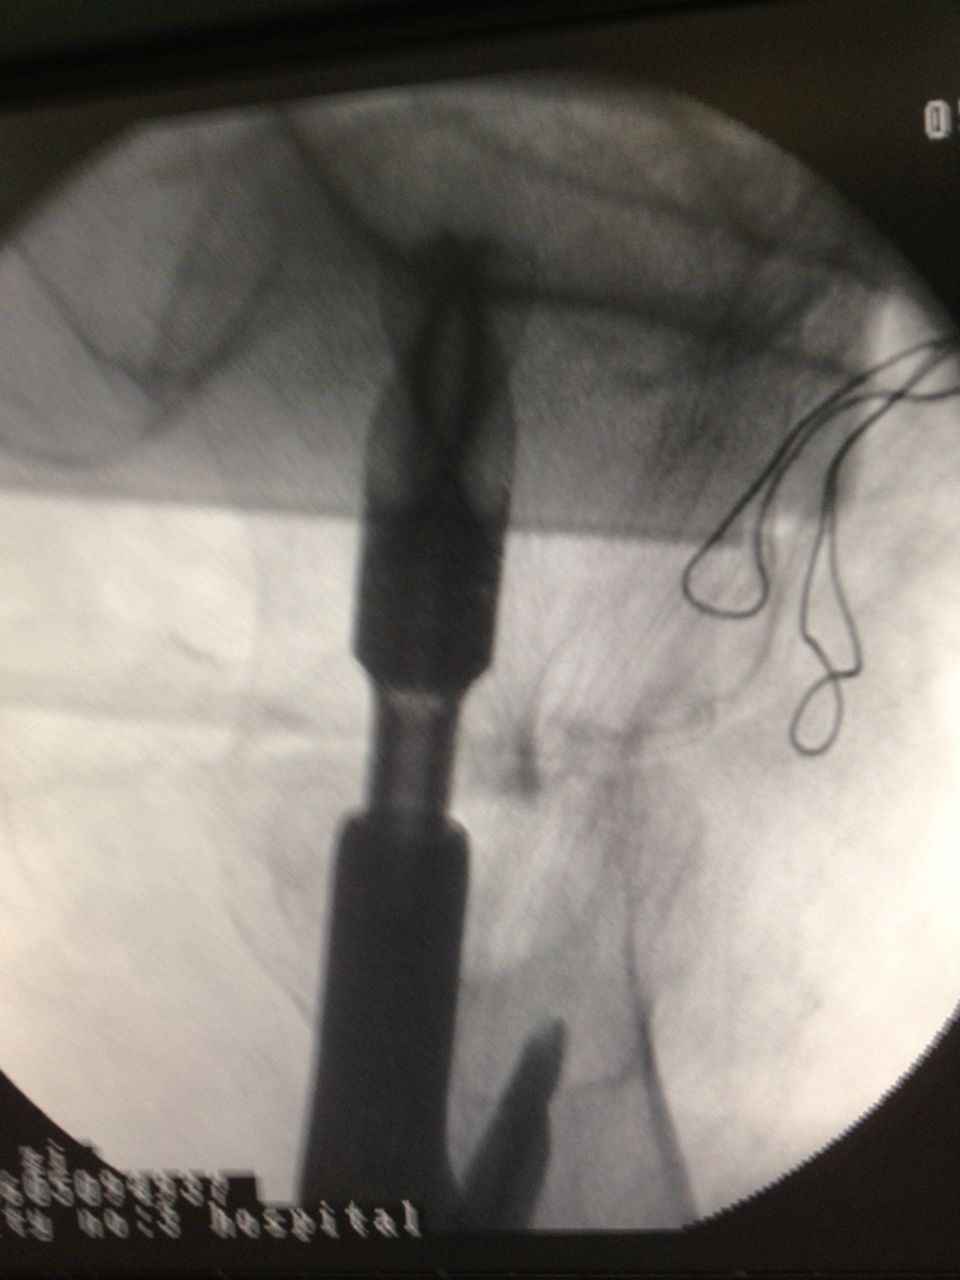

骨科、心内科、麻醉科等多科专家组成的专家组认真仔细分析病情,决定采用髋关节微创植入内固定术。6月4日,老人接受手术,在手术牵引床上,通过C臂X光机透视,不切开骨折端闭合牵引复位,在老人骨折处复位到最佳状态时,刘忠国在骨折处开出5公分的口进行螺旋刀片动力髋固定,最大程度减少手术损伤,促进骨折端提早愈合。